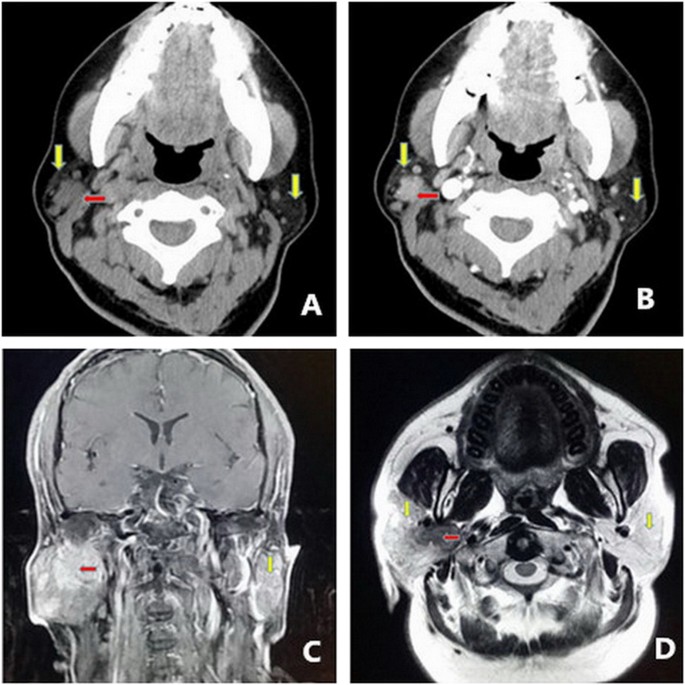

Large And Multiple Warthin S Tumors Of Bilateral Parotid Glands A Case Report Of Bilateral Regional Excision Of The Parotid Sciencedirect

Ct Features Of Parotid Gland Oncocytomas A Study Of 10 Cases And Literature Review American Journal Of Neuroradiology, Biopsy can provide relevant diagnostic information during the evaluation phase of salivary gland tumors. If the tumor contains cancer cells, additional treatments might be recommended. Although pleomorphic adenomas most commonly occur in the parotid. All tumors developed in the parotid gland. Parotid tumors often cause swelling in the face or parotid tumor treatment is usually with surgery to remove the tumor. The submandibular gland contains approximately 10%, with. Th e preferable gantry angul ati on to. Unexplained painless or painful growth of the parotid gland. In evaluating tumors of the parotid region , it is important to know whether they are intrinsic or extrinsic to the parotid gland and to establish the extent of the a se lec ti on of ct scan locations is made on this scoutview on the video d isplay using a mova ble c ursor. During fna, small glandular tissue samples are obtained and examined by microscopy to determine cellular. On ct scans the submandibular gland has a density that is isodense to slightly hyperdense relative to skeletal muscle. This specific type of tumor has a tendency to grow this type of tumor accounts for the vast majority of all parotid tumors. The vast majority of benign parotid tumors are pleomorphic adenomas, also known as benign mixed tumors. Most parotid tumors are noncancerous (benign), though some tumors can become cancerous. The gland does not become as fatty of all salivary gland tumors, the vast majority (80%) are found in the parotid gland.